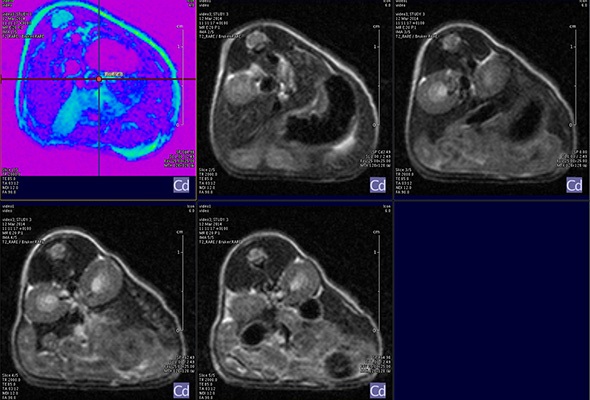

MRI is based on NMR Spectroscopy, which is the best language to talk to nature. We know how it is important to exploit different field strengths in order to extract maximum information from the system that we are investigating.

I think that also the low-field, let’s say the low/intermediate field to work at the 1 Tesla for instance as in the case of this beautiful Icon system, this gave us unique possibilities. Anytime we use a gadolinium-based agent or more in general a paramagnetic basic agent the best field is the 1 Tesla.

So, we can show that there is a real advantage of working at 1 Tesla in comparison to for instance 7 or 9 Tesla when one is using a relaxation enhancer to target a specific epitope in the region of interest.

Using the ICON™ Powerful MRI, Simplified.

For more information please visit: Bruker ICON™